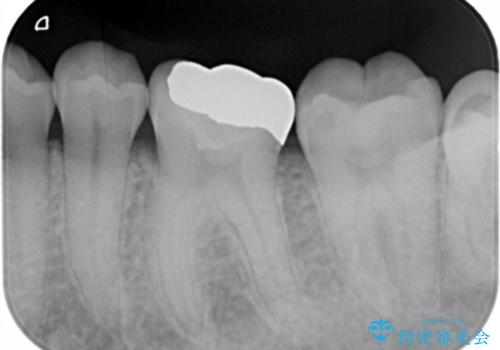

- ゴールドアンレー 11万円費用は治療当時の料金となります

セラミックの詰め物は範囲が多ければ多いいほど割れてしまうリスクが高いため

被せ物(ジルコニアクラウン)のご提案をさせて頂く場合があります。

今回はなるべく歯質を残したいとの事なのでゴールドの詰め物でご案内させて頂きました。ゴールドは範囲が多くても割れる心配がありません。また、虫歯の再発リスクが低いです。